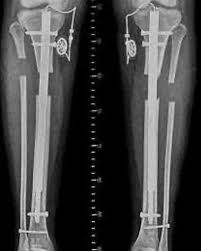

O transporte ósseo é uma técnica reconstrutiva avançada utilizada no tratamento de grandes perdas ósseas segmentares, decorrentes de traumas complexos, infecções (osteomielite), ressecções tumorais ou falhas após cirurgias múltiplas. Baseia-se no princípio da osteogênese por distração, em que um segmento ósseo viável é gradualmente deslocado através de um fixador externo ou de sistemas assistidos por placa, estimulando a formação de novo osso no espaço criado.

No CBOT, aplicamos protocolos individualizados com fixadores circulares ou monolaterais, conforme a localização e o tipo de defeito. Em casos selecionados, utilizamos abordagens híbridas que combinam fixação interna e regeneração óssea guiada, reduzindo o tempo total de tratamento e aumentando o conforto do paciente.

Correção simultânea de deformidades e encurtamentos;

A técnica representa uma das mais eficazes estratégias biológicas na reconstrução de perdas ósseas críticas, promovendo recuperação anatômica, estabilidade mecânica e restauração funcional completa.